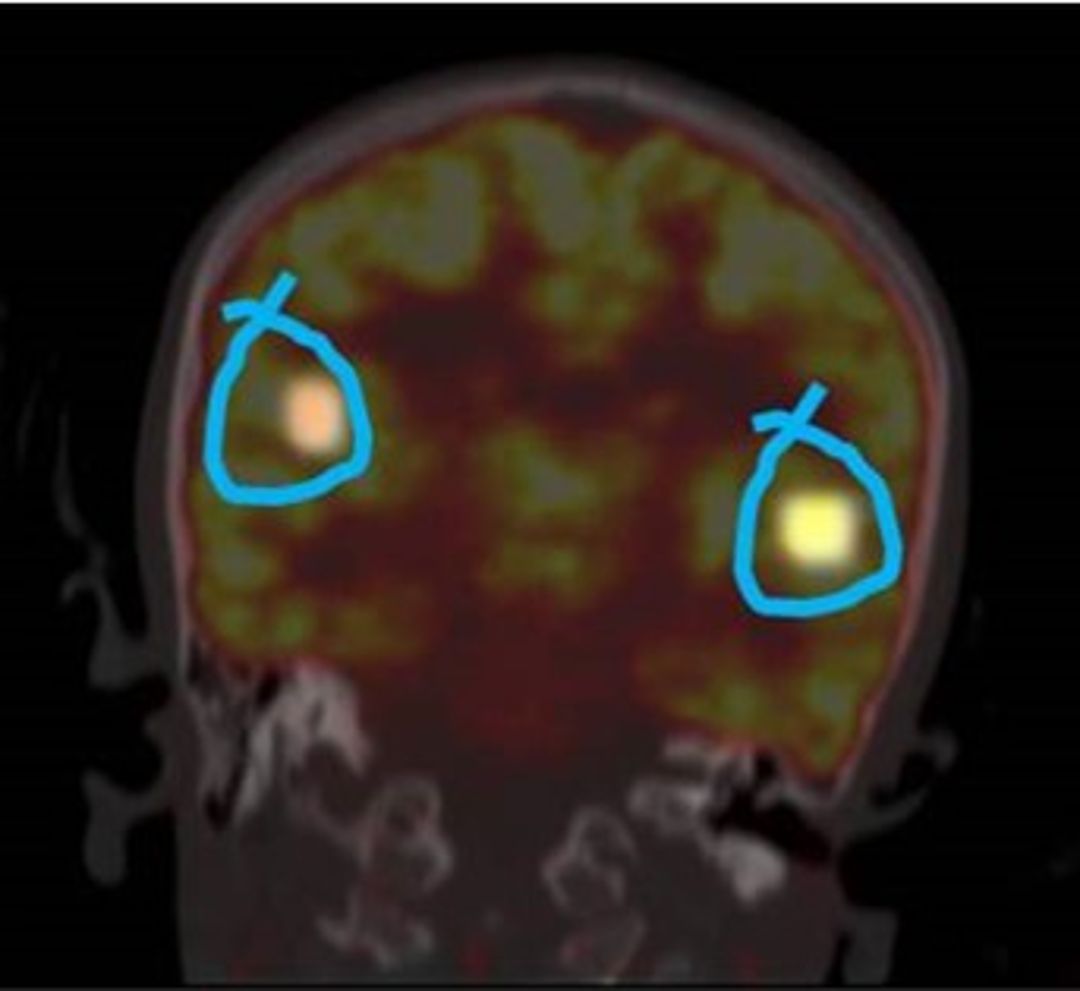

The study included 40 patients with median age of  5.6Yrs (range 4-16). of these 40, 24 (60%) had DO and 16 (40%) UD. In cases of detrusor overactivity TcPTNS decreased the activity in the mid-cingulate gyrus, hypothalamus, premotor cortex    and lateral pons (fig, 1a & b). These areas in brain are reported to be involved in the process of micturition.  On the contrary avid uptake was noted in lateral cingulate gyrus, mid pons and periaqueductal grey [PEG] in cases of underactive detrusor (UD) (fig. 2a). Hyper metabolism in these areas has been recorded during strong urge for micturition.

Contrarily avid uptake was noted in lateral  cingulate gyrus, mid pons and periaqueductal grey [PEG] in cases of underactive detrusor.   Increased brain activity and hypermetabolism  in these areas has been recorded during strong urge or the act of micturition (Bhide et al., Int Urogynecol J

. 2019).

Figure 2 Avid uptake was noted in lateral cingulate gyrus, mid pons and periaqueductal grey [PEG] in cases of underactive detrusor